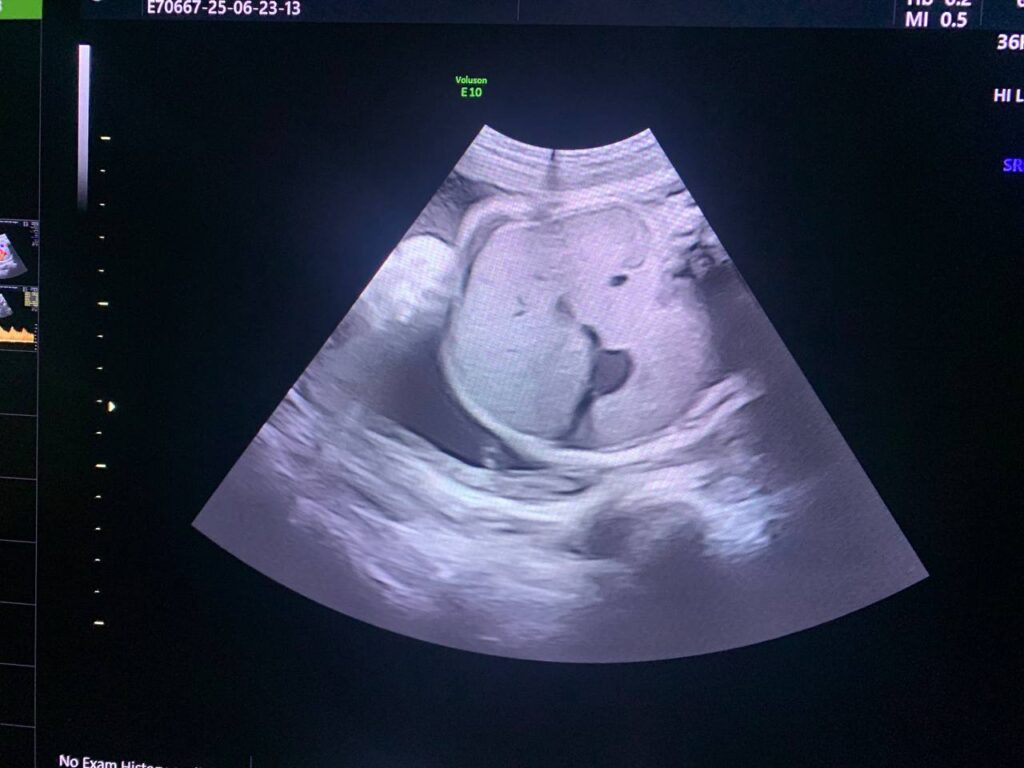

small cystic mass 9x4mm , in the posterior fossa , Blake’s pouch cyst , can not be excluded

This same patient at 26 wk